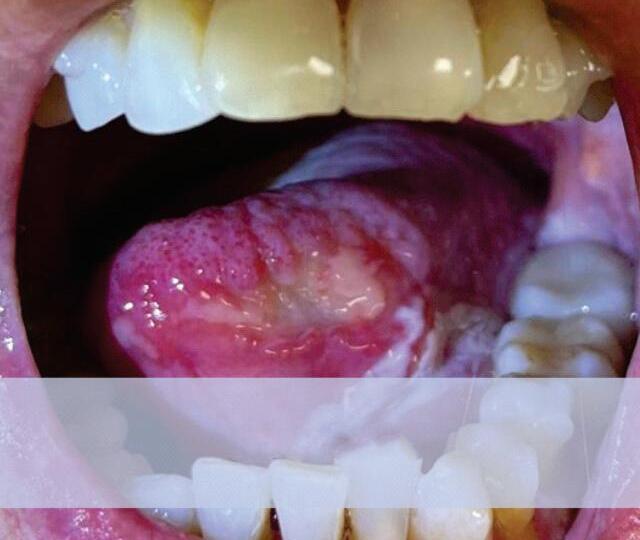

21-8. apresentação clínica das lesões potencialmente malignas.